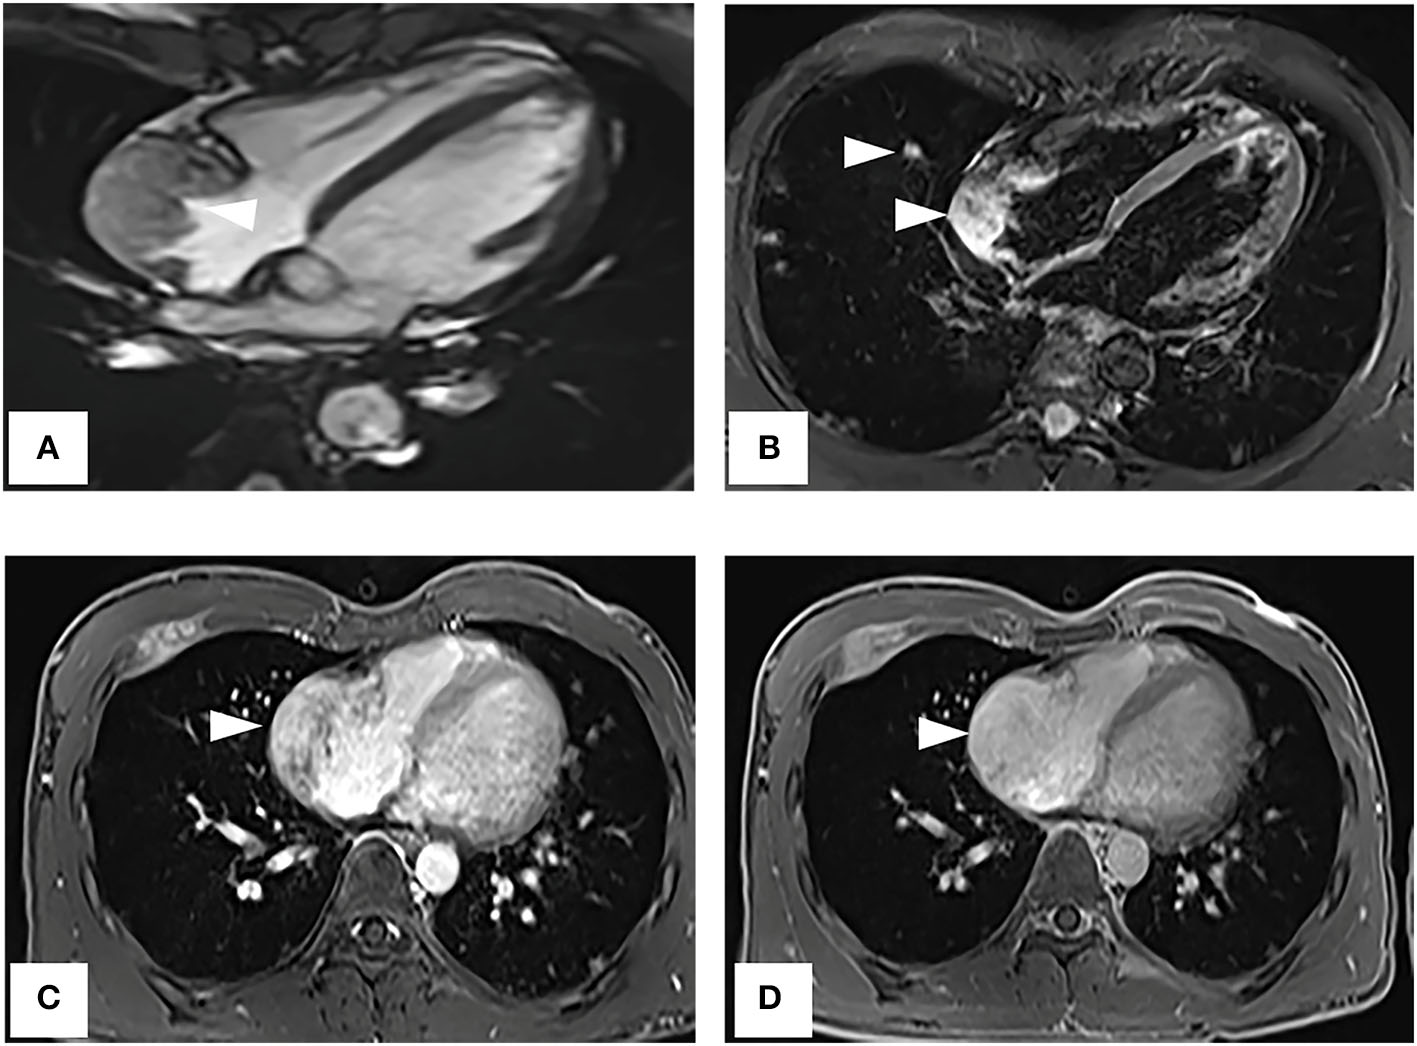

A CT examination from the chest to the pelvis was performed, which revealed a right atrial mass, multiple small ground-glass pulmonary nodules, and bone destructions (Figures 1A–D). Transthoracic echocardiography (TTE) showed an ill-defined hypoechoic mass of approximately 3.8 cm × 2.3 cm, attached to the lateral wall of the right atrium. Cardiac MRI (CMRI) exhibited a right atrial tumor and multiple pulmonary lesions. On steady-state free precession (SSFP) cine imaging planned in the four chambers, the tumor showed isointense (Figure 2A). On T2-short tau inversion recovery (STIR) sequence images, the tumor displayed high-signal intensity (Figure 2B). On enhanced MRI, the tumor showed arterial heterogeneous enhancement and progressive but incomplete enhancement in the delayed phase (dynamic acquisition) (Figures 2C,D). The patient was referred for 18F-fluorodeoxyglucose (FDG) positron emission tomography-CT (PET-CT) for further characterization of the cardiac mass and systemic evaluation. PET-CT images demonstrated that the right atrial tumor had intensely increased FDG uptake (standardized uptake value, SUVmax, 8.4) with signs of pulmonary and bony metastases (Figure 3). These preoperative images characterized the mass as highly suspicious for a malignant cardiac tumor with multiple metastases.

Figure 2

Cardiac magnetic resonance imaging. (A) On SSFP cine imaging planned in the four chambers, the tumor shows isointense (arrowhead). (B) On T2-short tau inversion recovery sequence images, the tumor displays high-signal intensity (arrowhead). (C,D) On enhanced MR imaging, the tumor shows arterial heterogeneous enhancement and progressive but incomplete enhancement in the delayed phase (dynamic acquisition).

Cardiac MRI is considered to be the most sophisticated imaging method to display the cardiac tumor size, location, and signal characteristics (15). T1-weighted images show tumor as predominantly isointense to the myocardium and high signal on T2-weighted images. Late gadolinium-enhanced (LGE) is avid and may predominate along prominent vascular channels to give a characteristic “sunray” pattern (2). In our case, CMRI clearly showed the tumor-infiltrating the free wall of the RA with obvious heterogeneous enhancement indicative of malignancy.